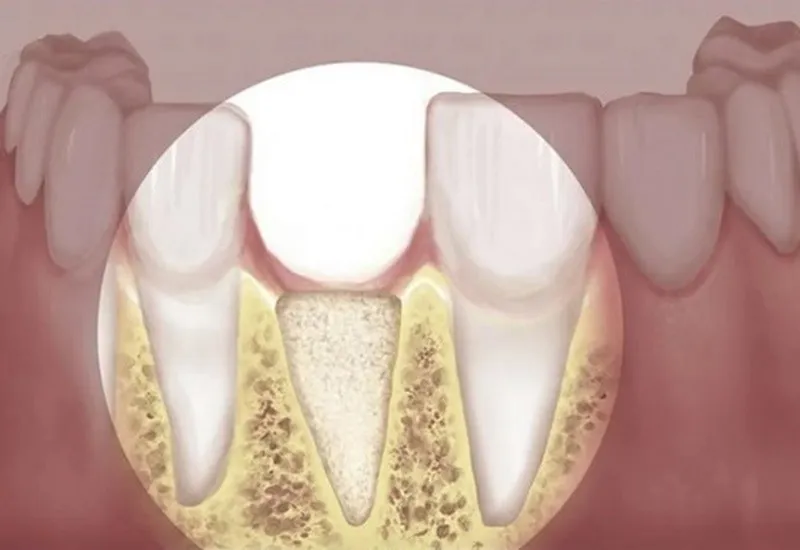

Tiêu xương hàm là hiện tượng nhiều người gặp phải khi bị mất răng. Hiện tượng này nếu để lâu có thể dẫn đến việc bị tụt